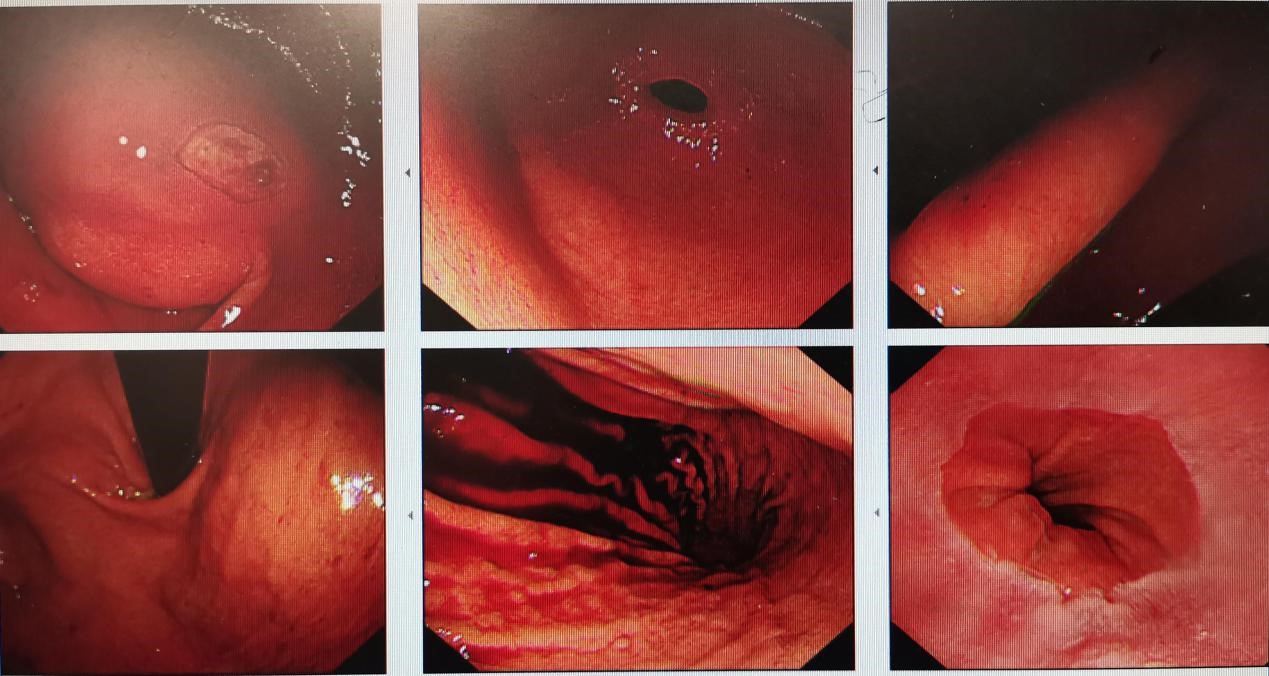

②胃镜:急性上消化道出血,十二指肠降段肿物并溃破出血。

急性上消化道出血,十二指肠降段肿物并溃破出血

胃肠镜——普通胃镜下胃肠道间质瘤的表现为粘膜下半球形隆起;粘膜表面光滑,也可伴有局部糜烂和溃疡;